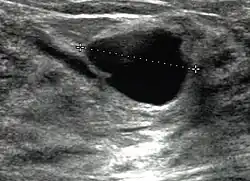

Mammazysten entstehen häufig schnell und können von Patientinnen aufgrund des knotigen Tastbefunds fälschlicherweise für Brustkrebs gehalten werden. Die diagnostische Abklärung erfolgt durch Mammasonographie, bei der sich die Zysten als echoleere, klar umgrenzte Gebilde zeigen, deren Rand keine papillären Strukturen aufweist. In der Mammographie zeigen sich Zysten als scharf begrenzte Strukturen mit angedeutetem Halo-Phänomen. Unter Umständen kann eine Punktion (Feinnadelbiopsie) unter Ultraschallkontrolle mit zytologischer Untersuchung des Sekrets angezeigt sein.